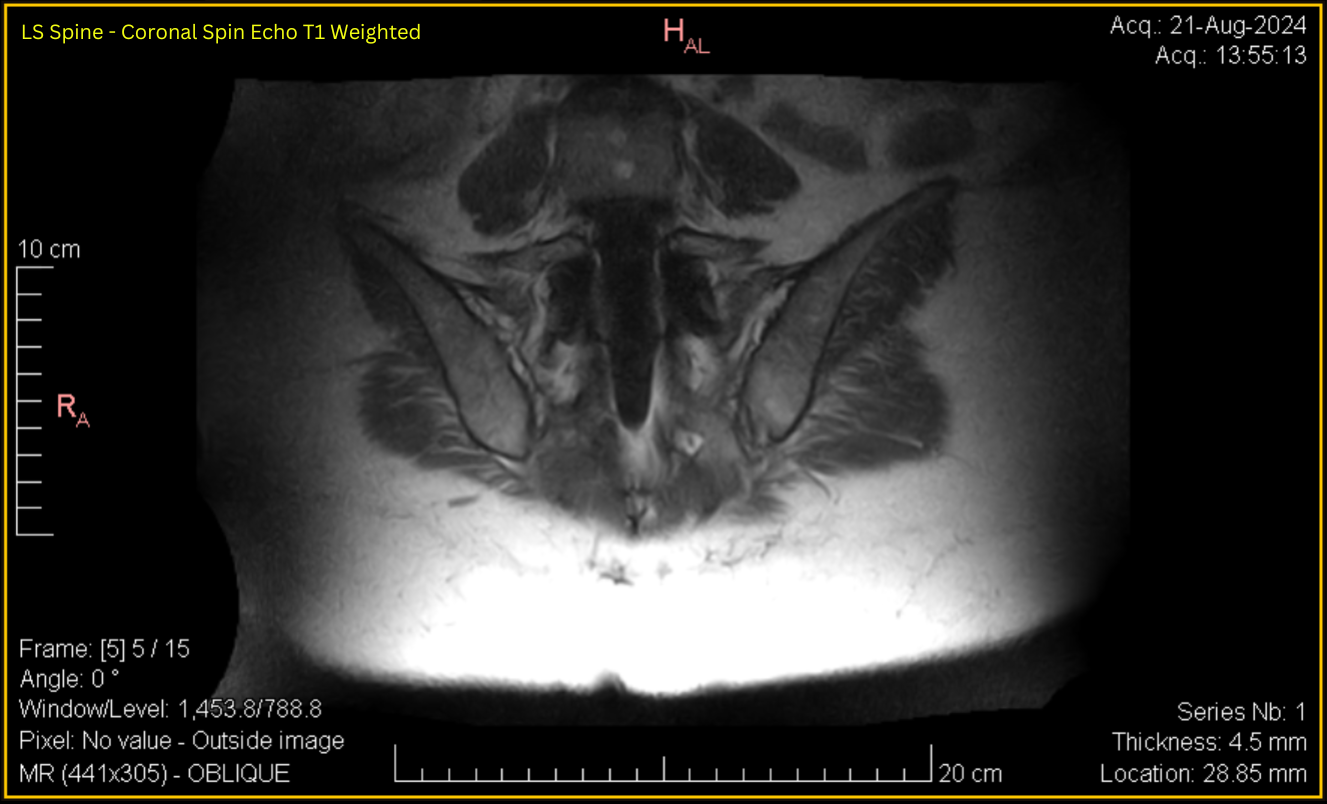

Sacroiliac – Coronal SE T1

LS Spine - Coronal Spin Echo T1 Weighted Oblique (Contrast & brightness adjusted for clarity as below)

See Full DICOM Info and image adjustments

Expand

Click to view full size image